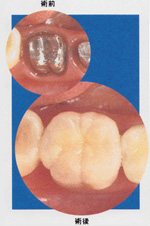

笑うと金属が見えるのが気になるというお悩みをお持ちの方へ

~金属を使わない治療(メタルフリー)へのご提案~

| 症例1 |  |

|

|

| 症例2 |  |

|

|

| 症例3 |  |

|

|

| 症例4 |  |

|

|

| 症例5 |  |

|

金属の詰め物(保険適用のもの)は、審美的(見た目)な問題だけでなく、硬すぎる為に機能的(咬み合わせ)にもあまりおすすめ出来ません。

また、気付かない間に感作(体が金属に対して反応するようになる事)して、金属アレルギーを起こし肌あれ等の原因になっている事があります。